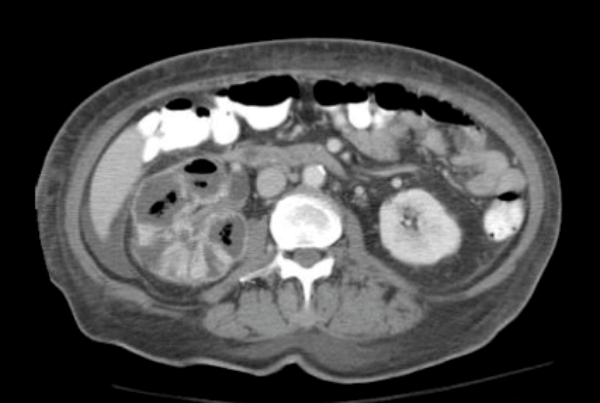

These are a series of radiological images highlighting serious urological infections.

C.

- What are the radiological diagnoses from these images?

Case 3

c: emphysematous pyelonephritis.